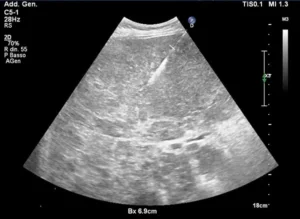

La procedura viene eseguita sotto guida di tecniche di imaging come:

- ultrasuoni (US)